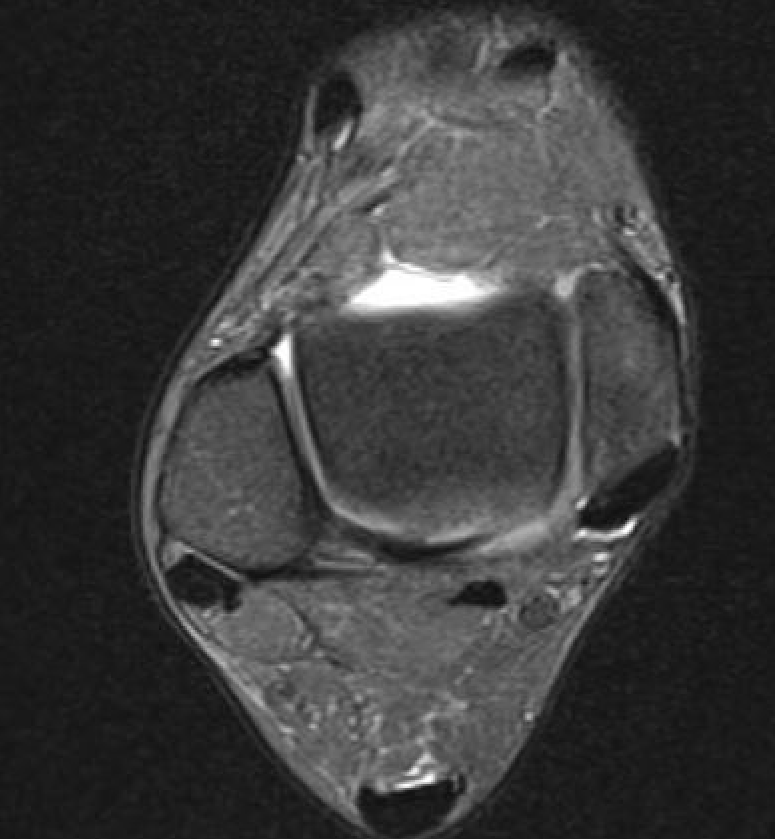

PTFL